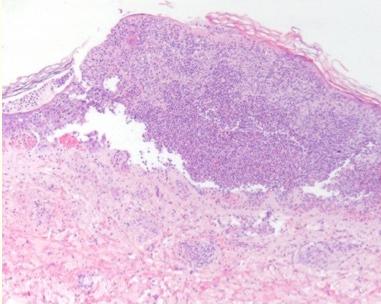

出院3周后,患者随诊诉*丸睾**疼痛15天,体重减轻(5KG)。体格检查发现腿部多发紫癜性病变伴溃疡、脓疱及溃烂(图1和2),手臂也发现瘀斑。皮肤活检显示角膜层脱落,角质形成细胞坏死和丰富的多形核细胞(图3),深部真皮及皮下动脉的多形核浸润伴血管炎的局灶性体征(图4),与结节性多动脉炎一致。患者接受泼尼松治疗,从60 mg开始,然后逐渐减少剂量,直到皮肤病变完全缓解。

图4HE染色显示动脉多形核浸润和血管炎的局灶性征象